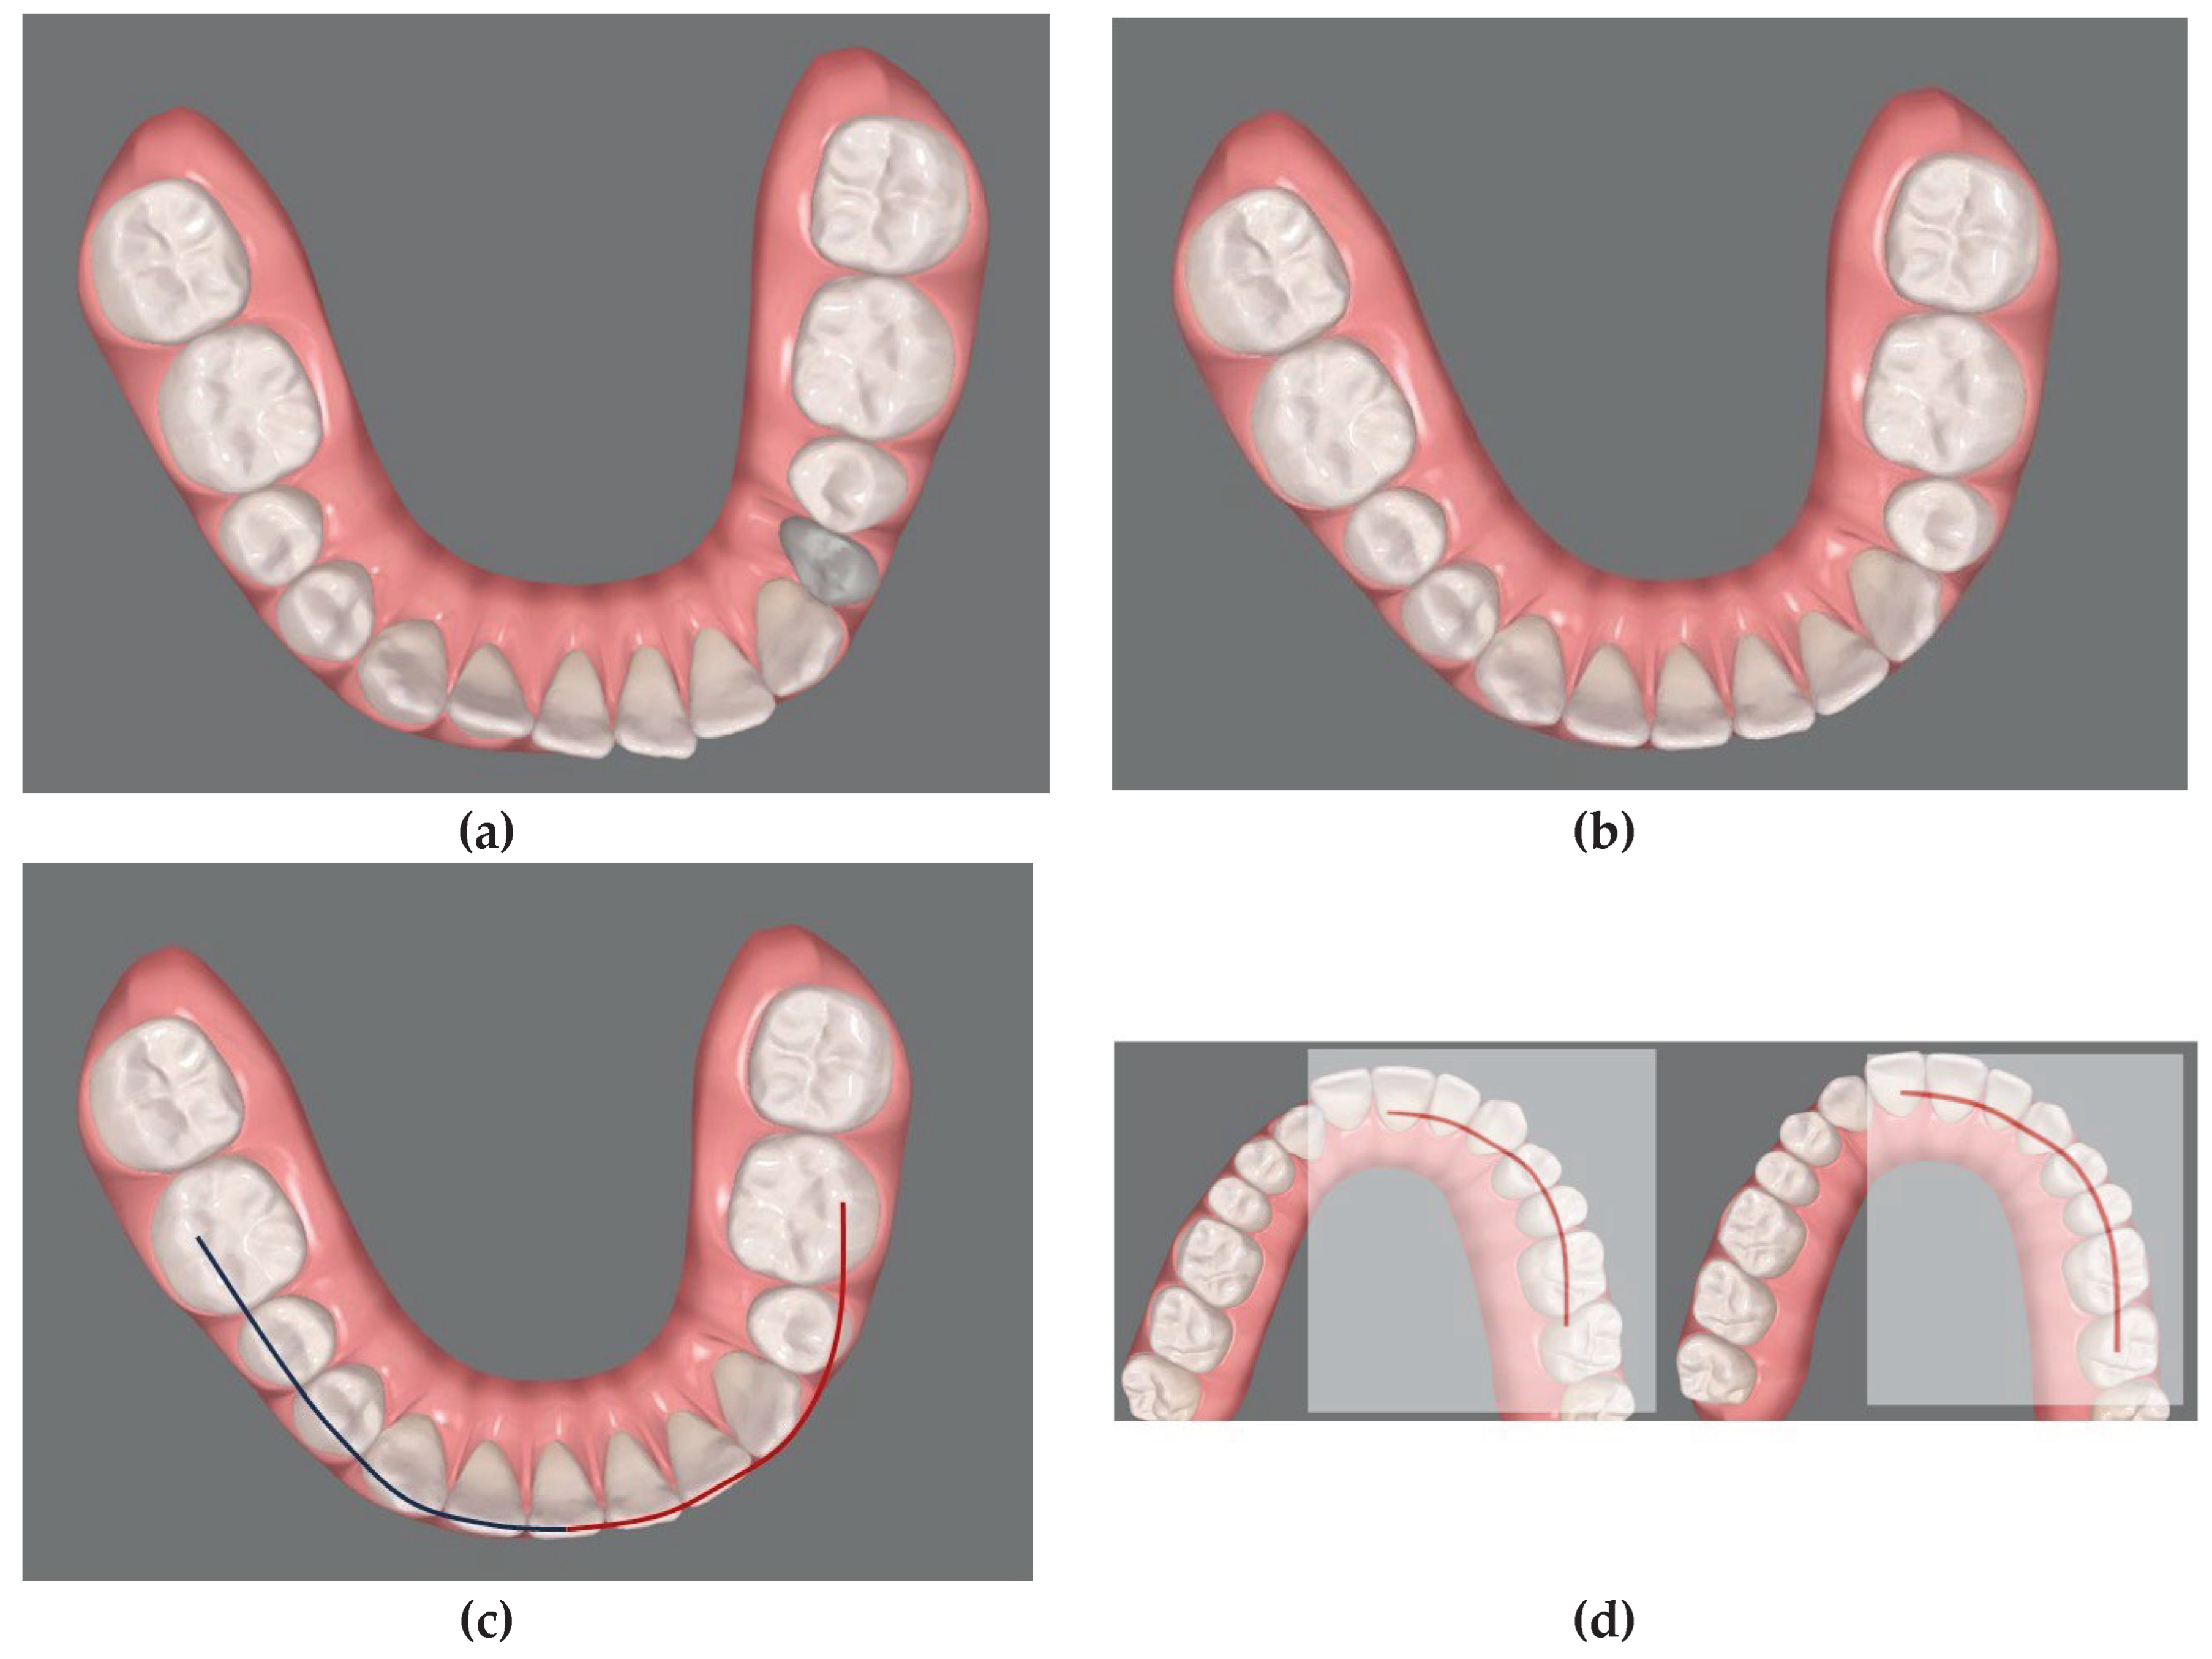

Virtual scanning were performed for each patient and a personal virtual file of the arches was elaborated with ClinCheck® Software (Align Technology, Inc., San Josè, California) (Figure 1). ClinCheck® Software allows to manipulate the location of each tooth, independently. Since this software does not allow simulation of maxillary segmental osteotomies, to coordinate the segments of the maxillary arch to the mandibular arch, a simple 3-step method similar to an occlusogram [17] that includes the following actions was developed:

1st step: Align the mandibular teeth in the correct final position eliminating compensations where needed. (Figure 2 a)

2nd step: connect the cuspids of the lower arch in order to obtain the guide curves. (Figure 2 b)

3rd step: Superimpose these curves on the upper arch segments to determine the corresponding final dental positions to be achieved during the Clin Check (Figure 2 c, d) obtaining the presurgical occlusion (Figure 3).

Figure 2. Method developed to coordinate the segments of the maxillary arch to the mandibular arch: (1st step; a-b) initial position of the mandibular teeth and alignement of the mandibular teeth to the correct final position eliminating compensations. (2nd step; c) drawing of virtual curves following the final aligned image of the lower arch. (3rd step; d-e) superimposition of the curves on the maxillary arch segments in order to guide the corresponding dental movements to be carried out during the ClinCheck.